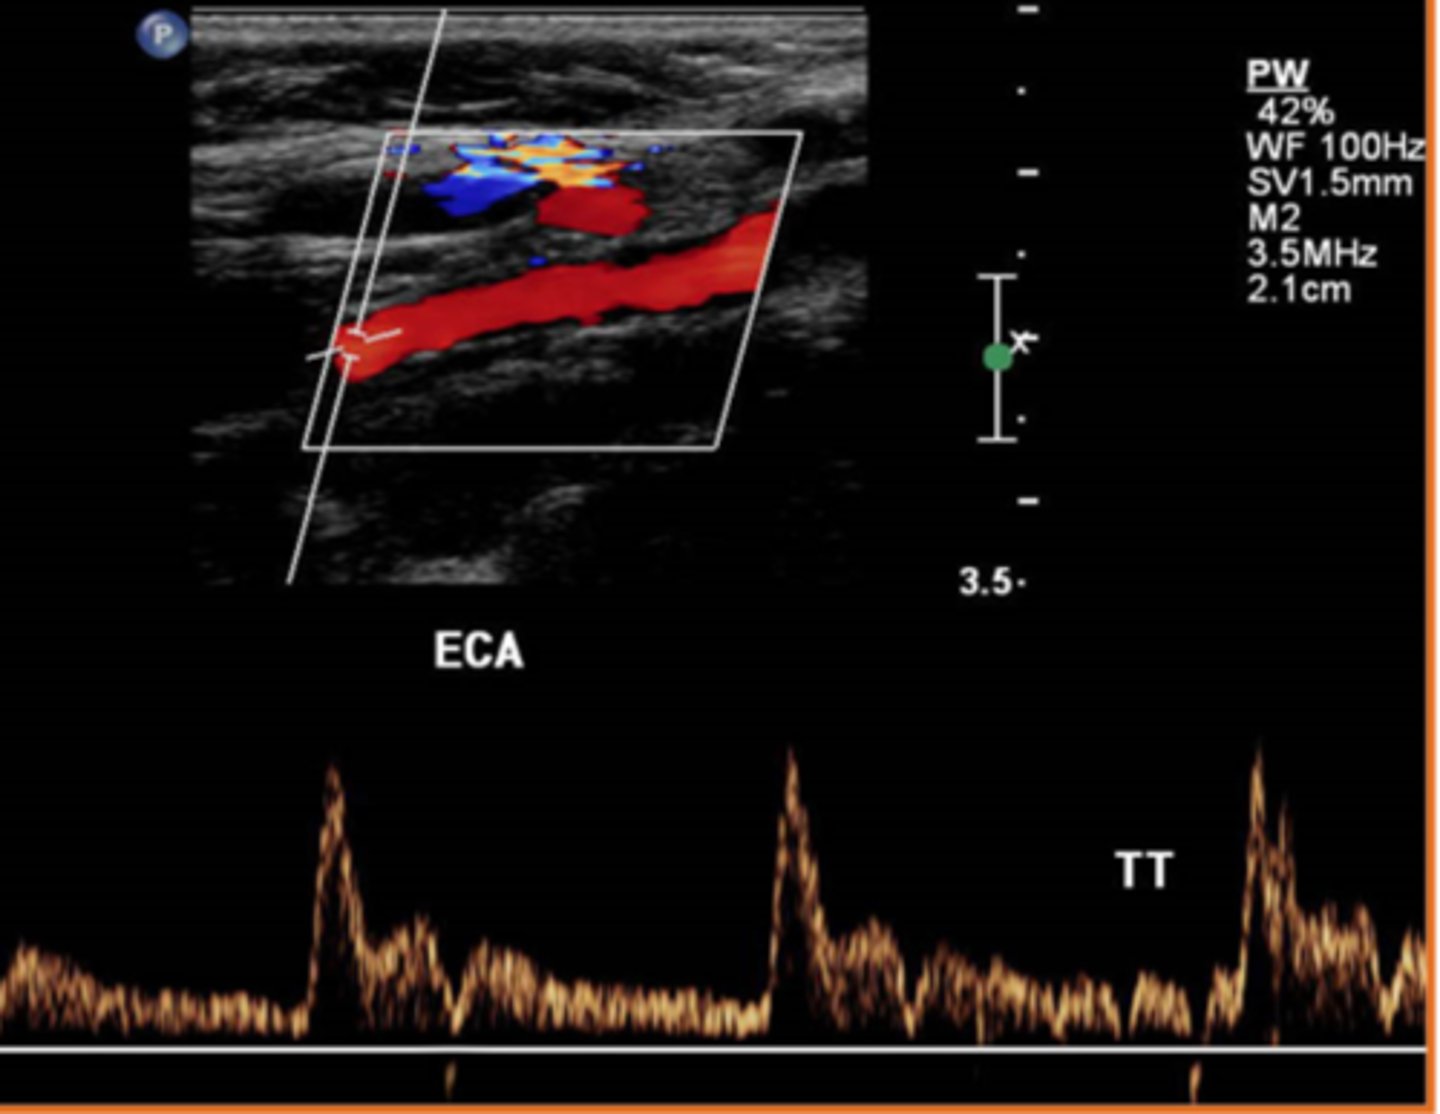

It is extremely important for sonographers to recognize the difference between blood flow patterns associated with the Internal Carotid Arteries that bring blood to the brain and the External Carotid Arteries that bring blood to the face and scalp. If a sonographer were to describe the flow in a high resistance vascular bed and how that would look on a spectral Doppler waveform, the sonographer might say...

the spectral Doppler tracing accelerates to a peak in systole and then touches the baseline during diastole

the spectral Doppler tracing accelerates to a peak in systole, decelerates in diastole, but does not touch the baseline